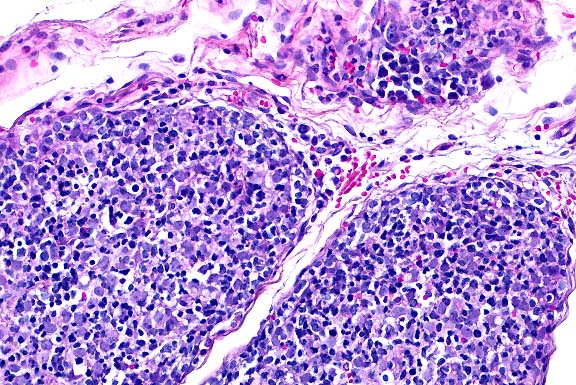

4x

obj

- Case 19-4. Mammary gland. Glandular acini are hyperplastic,

multifocally ectatic, and separated by increased amounts of loose

fibrous connective tissue stroma.

- AFIP Diagnosis: Mammary gland: Hyperplasia, ductal

and stromal, diffuse, moderate to marked, WHHL rabbit, lagomorph.